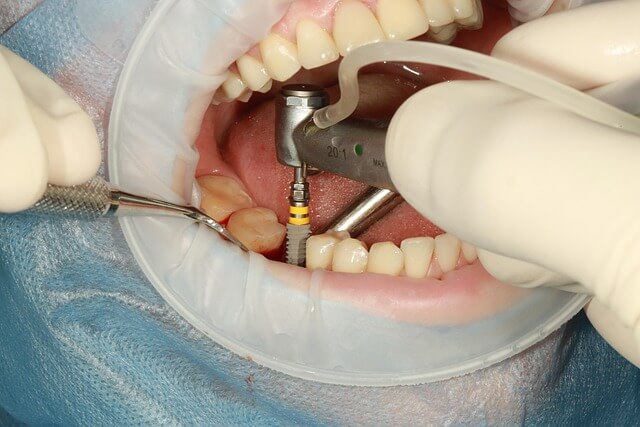

2. 잇몸이 내려 앉을 때 잇몸 복원치료 방법

* 잇몸이 내려 앉을 때 복원치료에는 여러 방식이 있습니다. * 제가 들은 가장 기본적인 방법은 잇몸을 덮어주는 재생 치료인데, 이는 잇몸이 내려 앉을 때 잇몸 조직을 보호해주는 역할을 합니다. * 실제로 치료를 받은 한 지인은 시림이 거의 사라지고 다시 편하게 음식을 먹을 수 있었다고 했습니다. * 치료 과정은 개인마다 다르지만, 전문가의 손길을 통해 진행되는 만큼 일상에서 관리하기 어려운 부분까지 충분히 보완할 수 있습니다.

- * 잇몸 재생을 돕는 보강 치료

- * 노출된 치근을 보호하는 방법